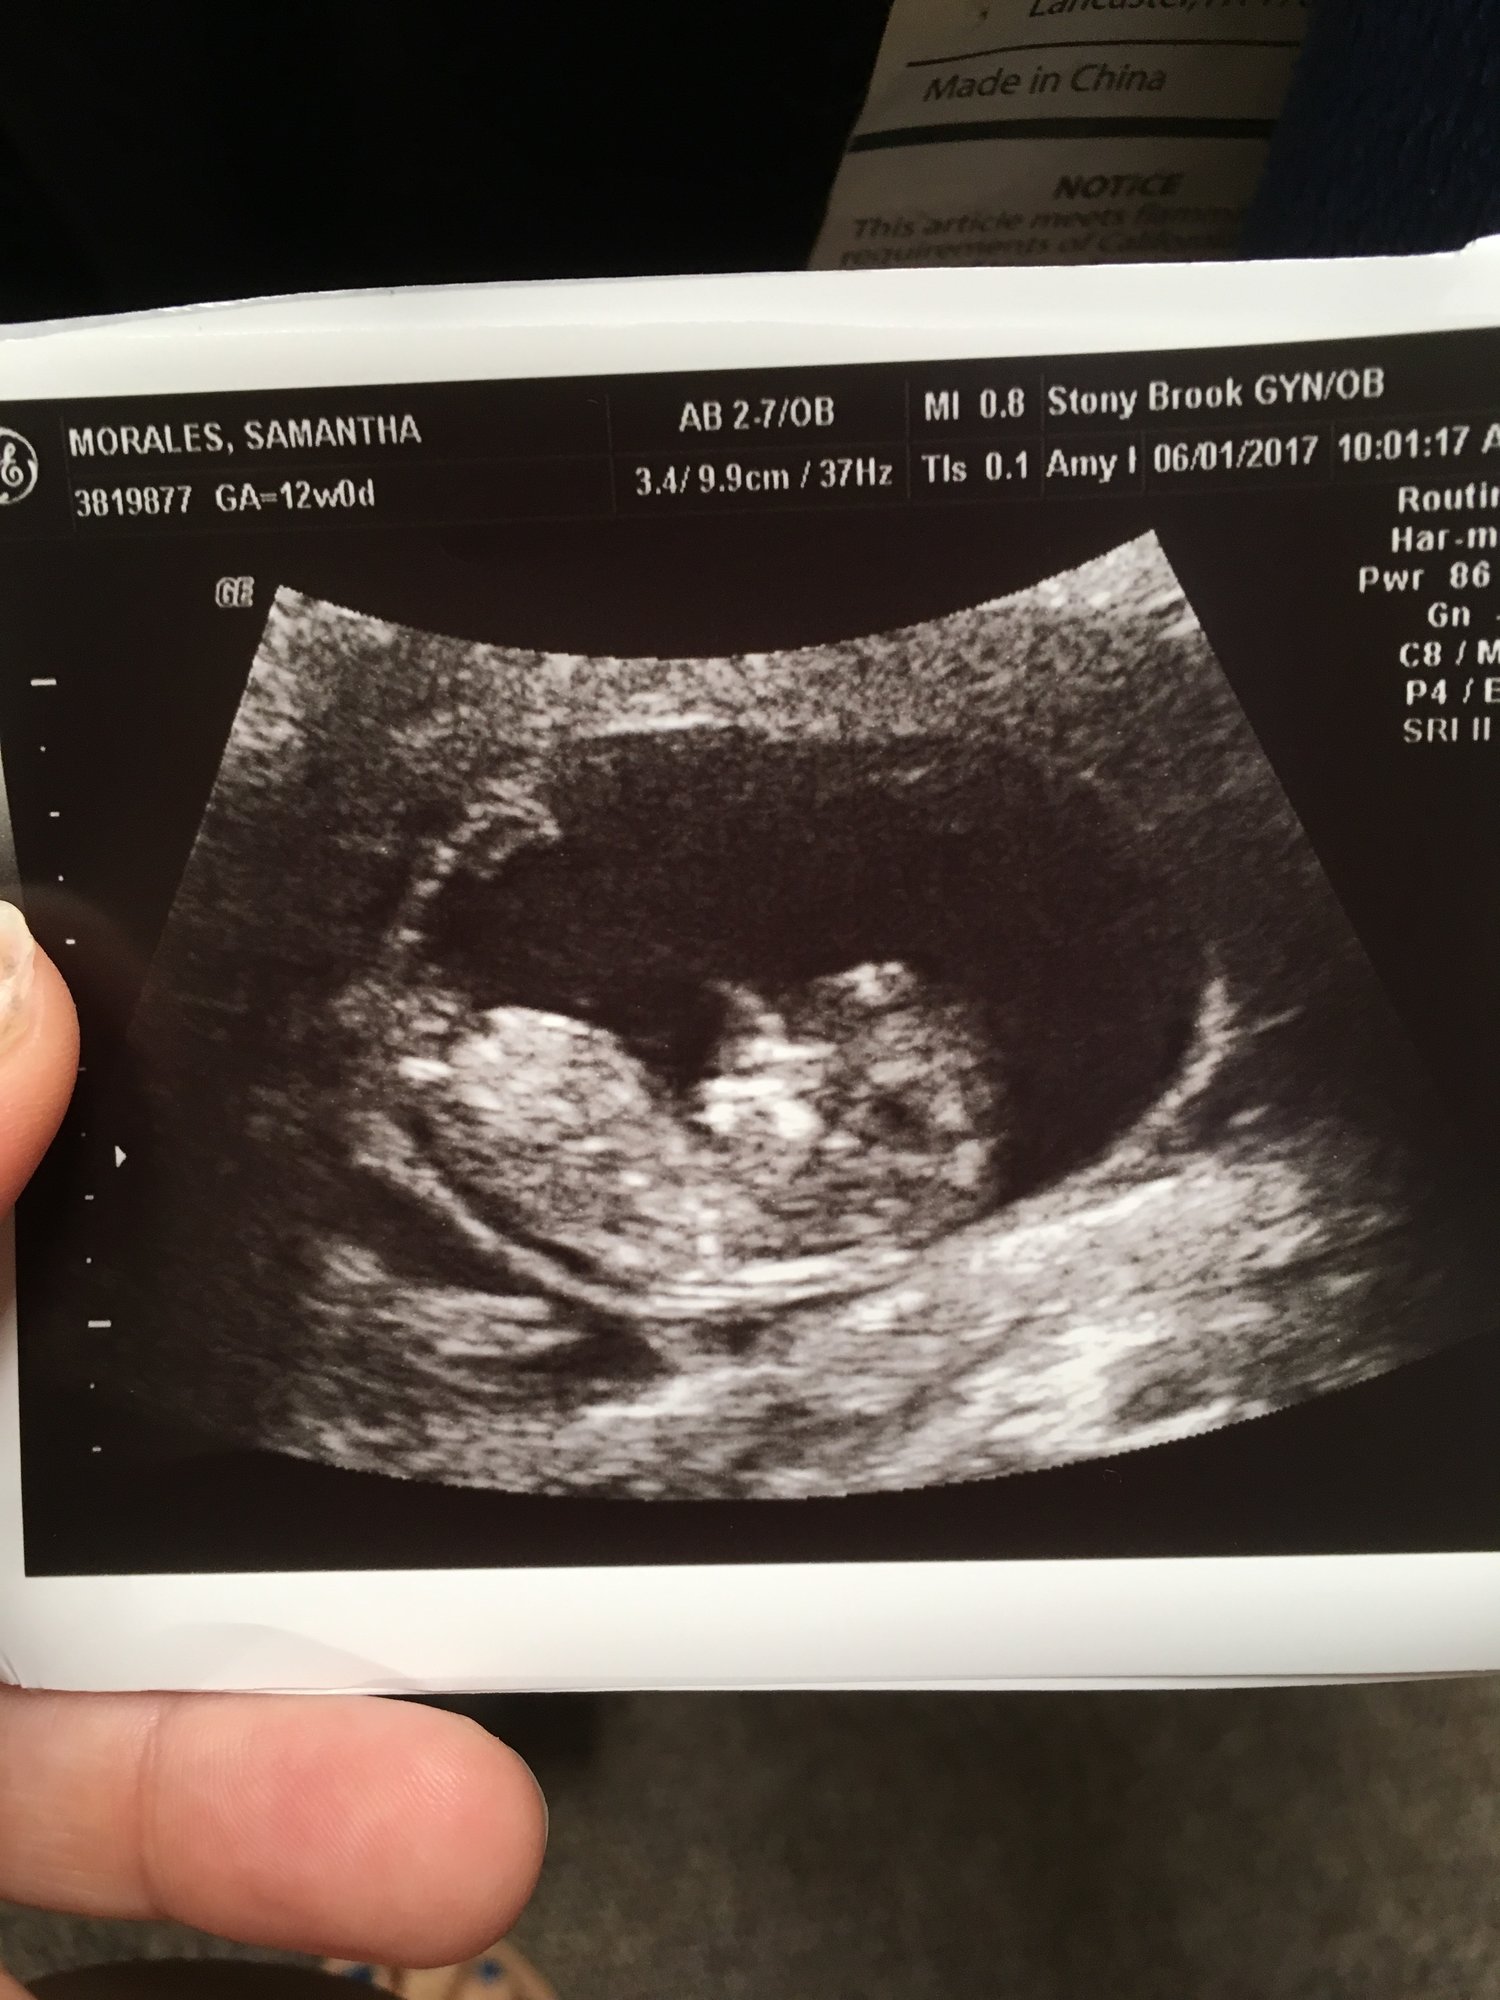

Agree with everyone else. I'm sure it's there, but I see no nub. It's just too early to distinguish anyway. If you absolutely can't wait until the anatomy scan, there are places you can get an elective ultrasound sooner.

but, seriously, at the VERY least you need to black out your personal information on your picture. be safe.